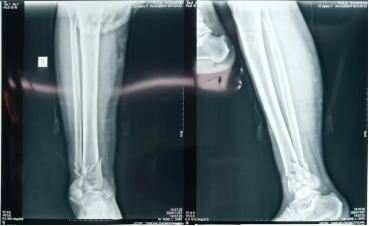

患者,女,75歲,主訴:踝部疼痛、腫脹,活動受限5天余。查體:右踝部畸形、腫脹明顯,局部按壓可觸及異?;顒蛹肮遣粮校钻P(guān)節(jié)活動明顯受限,足背動脈搏動可,足趾末梢血運及感覺尚可。診斷為右Pilon骨折見(Ruedi-Allgower III型)。

術(shù)前X線圖